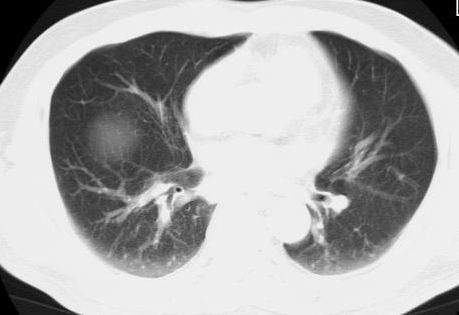

标题: CT15869:男性,71岁,因咳嗽而就诊,请讨论右上肺病变性质 [打印本页]

标题: CT15869:男性,71岁,因咳嗽而就诊,请讨论右上肺病变性质

患者,男性,71岁,因咳嗽而就诊,

典型的右肺中心性肺癌并纵隔淋巴结转移

右肺中心性肺癌并纵隔淋巴结转移可能性大!

考虑右肺中心性肺癌并右肺门及纵隔淋巴结转移。

1,右肺中心型ca,气管隆突旁淋巴结转移。